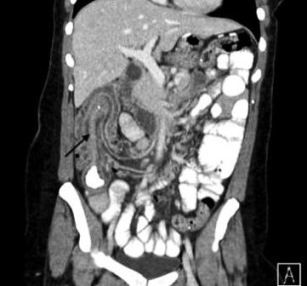

Figure 1 (click to enlarge)

A 30-year-old woman presented to the emergency department complaining of intermittent abdominal pain, nausea and vomiting, and passage of dark stool of several days’ duration. CT scan of abdomen and pelvis showed the terminal ileum “telescoping” through the ascending colon (Figure 1; Figure 2, arrows) confirming presence of ileocolic intussusception. A barium enema was attempted to reduce the intussusception but was only partially successful.